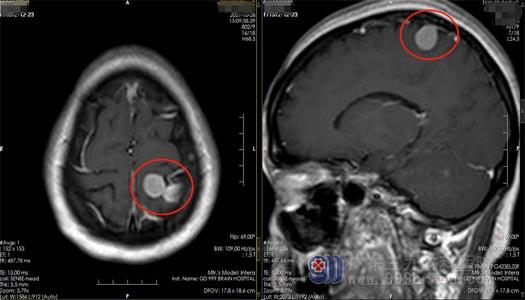

查先生,48岁,1个月前无明显诱因出现失神发作,表现为大脑一片空白,持续时间约1-2秒。近1个月来,他又发作两次,在当地医院查头颅MR,提示“左侧顶部多发占位病灶”,大小分别为17mm×10mm、15mm×13mm,考虑为脑膜瘤。

▲术前